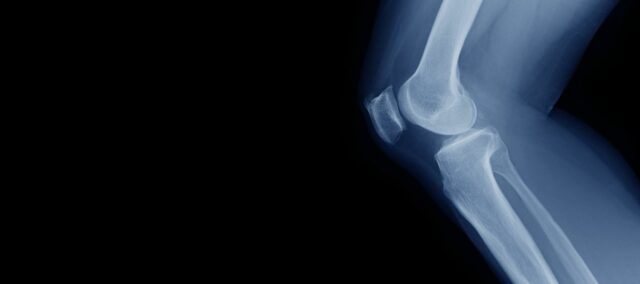

Утицај снаге квадрицепса на хрскавицу колена

Оптимална снага квадрицепса је неопходна за добро функционисање колена у свакодневном животу. Пошто је мишић квадрицепса важан стабилизатор и амортизер, он помаже у расподели оптерећења на зглобној површини колена. Ово је веома важно, посебно у светлу старења становништва и све већег броја људи са гојазношћу. Како тренутно не постоји прави лек за остеоартритис колена (ОА), кључно је успорити напредовање до ОА или – када је то могуће – спречити његов почетак. Стога се јачање заговара као третман прве линије за ОА колена. До сада се нису могли извући чврсти закључци о утицају снаге квадрицепса на хрскавицу колена. Ту почиње ова студија.